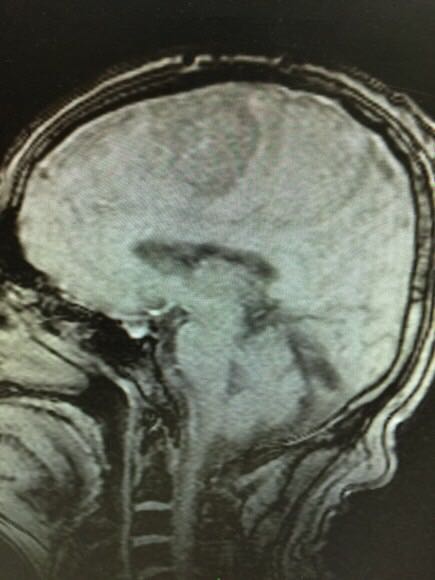

老年男性,头痛、言语不利半年余,查头颅MRI见颅内占位,无恶心、呕吐,无意识障碍。既往高血压、糖尿病病史,现控制尚可。大家考虑什么?